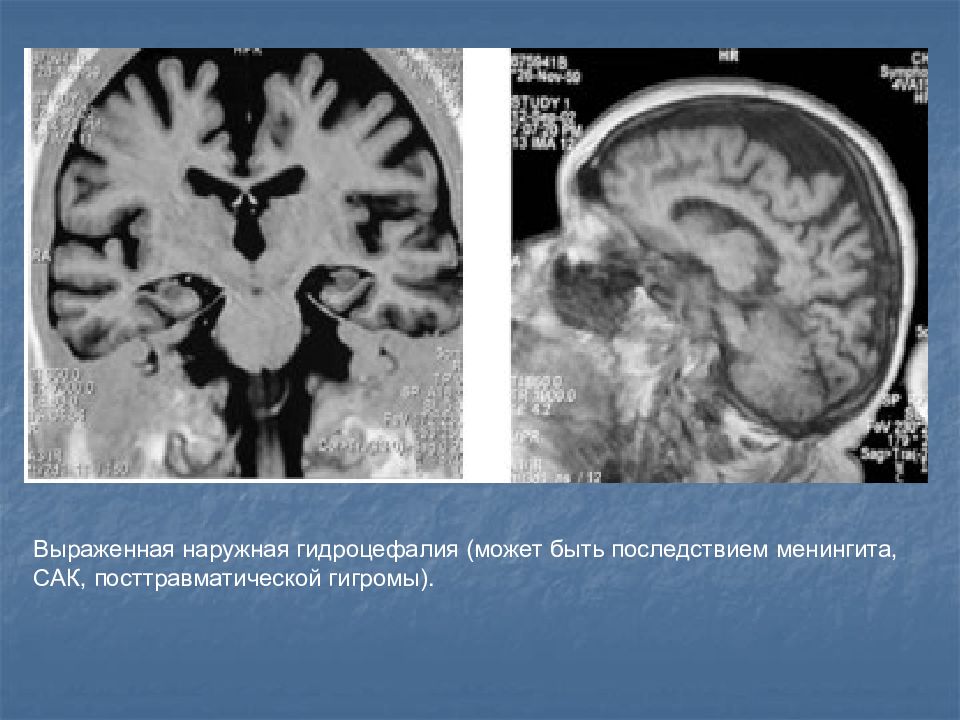

Признаки умеренно выраженной наружная

Признаки умеренно выраженной наружная 113 фото